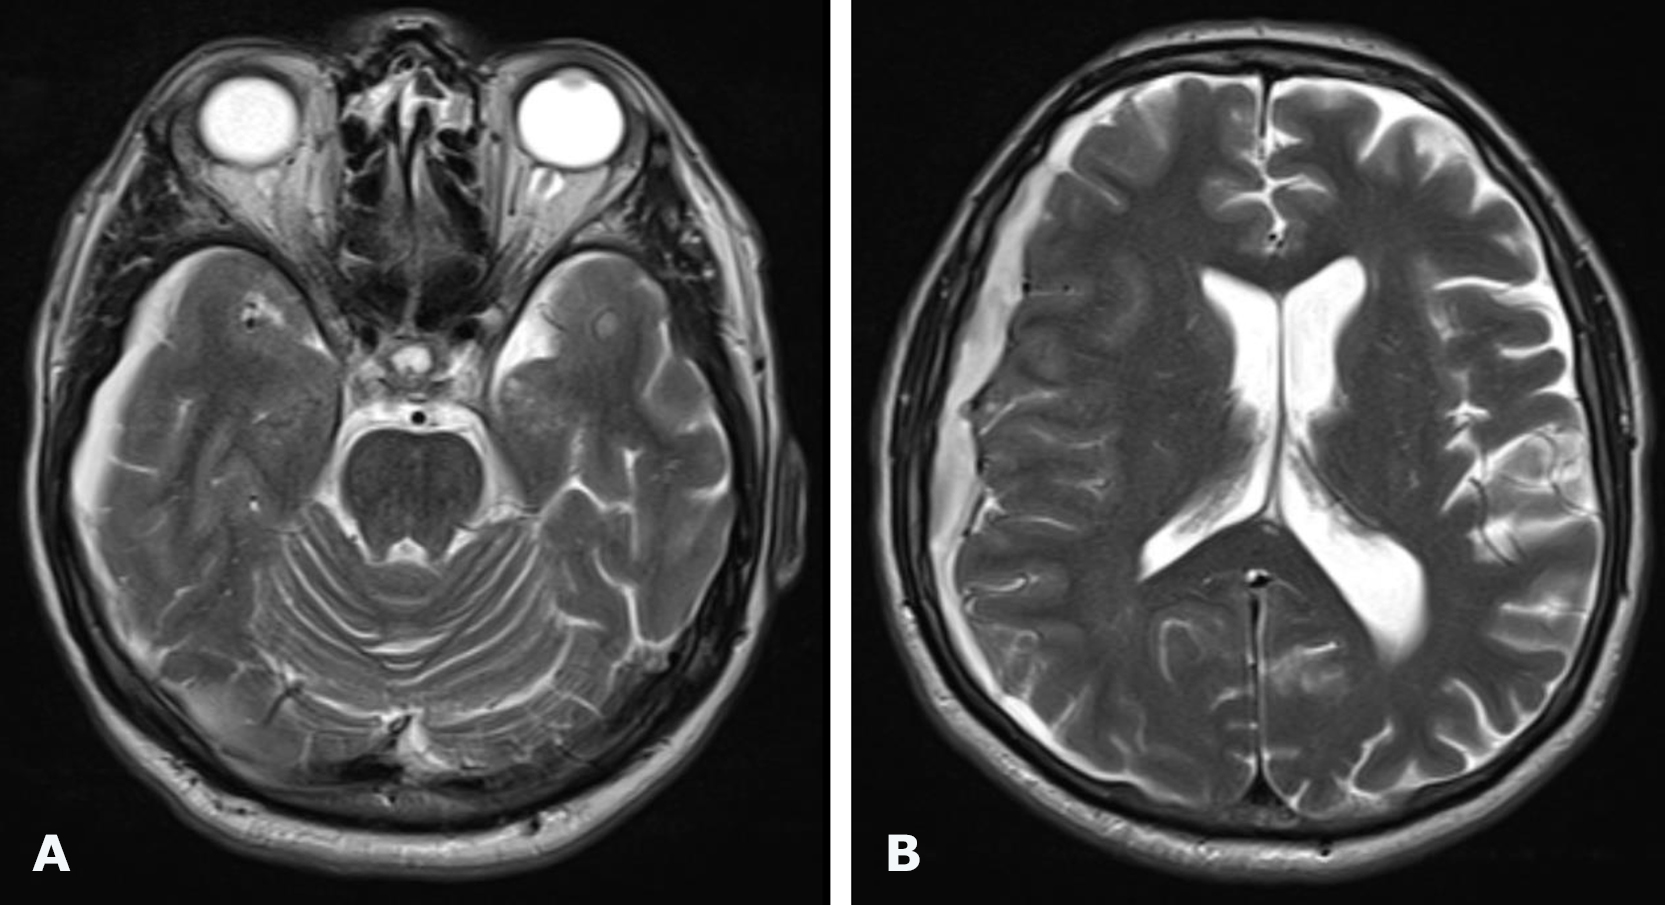

Brain MRI revealed a right-sided hemispheric chronic cSDH with dimensions (thickness/length/height) of 10/166/124 mm and a 4-mm midline shift to the left (Fig. 5).

Fig. 5. Preoperative brain MRI, T2-weighted images: A, B – axial projections demonstrating a right-sided hemispheric cSDH

Follow-up brain MRI was performed 3 months after surgery (Fig. 9). Complete resolution of the chronic subdural hematoma was observed, with restoration of the normal position of the midline brain structures. On T2-weighted images, a focus of ischemic stroke was visualized in the right frontal lobe within the vascular territory of the excluded branch of the right middle cerebral artery together with the aneurysm. At follow-up examination, no focal neurological deficits were present, and headache and dizziness had resolved.

Fig. 9. Postoperative (3-months) brain MRI, T2-weighted images: A, B – axial projections. The red circle indicates a focus of ischemic stroke in the right frontal lobe measuring 19 × 13 mm